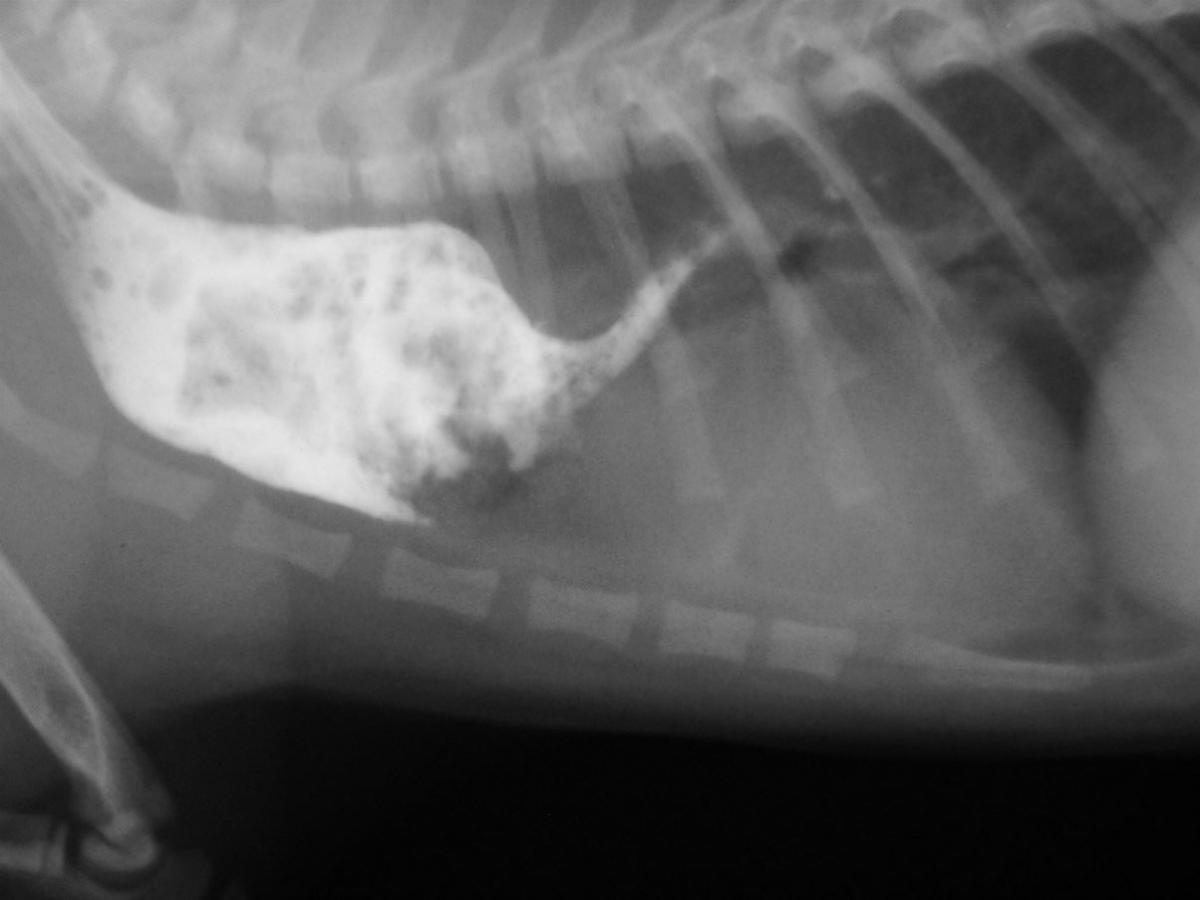

Generell führen wir Tumor und Fremdkörperentfernungen, Operationen am Gefäßsystem wie einen persistierender Ductus arteriosus oder einen persitierenden rechten Aortenbogen (PRAA) durch.